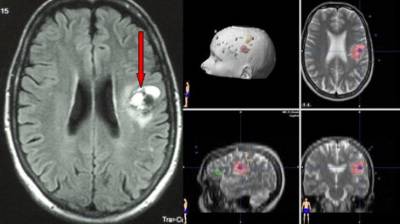

Врачи отмечают, что гемангиома головного мозга у взрослых является редким, но важным заболеванием, требующим внимательного подхода. Это доброкачественная опухоль, состоящая из кровеносных сосудов, которая может проявляться различными симптомами, включая головные боли, судороги и неврологические нарушения. Специалисты подчеркивают, что диагностика гемангиомы часто осуществляется с помощью МРТ, что позволяет точно определить ее размер и расположение. Лечение может варьироваться от наблюдения до хирургического вмешательства, в зависимости от клинической картины и состояния пациента. Врачи рекомендуют не игнорировать симптомы и обращаться за медицинской помощью при их появлении, так как ранняя диагностика и правильное лечение могут значительно улучшить качество жизни.

- Неинвазивные – магнитно-резонансная томография и компьютерная томография помогают получать объемное изображение, с помощью которого создается полноценный вид исследуемого органа.

МРТ

Отличается повышенной точностью полученных результатов, а также низким процентом погрешности, чего нельзя сказать об исследовании, основанном на использовании рентгеновских лучей.

Процедура полностью безболезненная и практически не имеет противопоказаний, за исключением наличия кардиостимулятора и периода беременности у женщин.